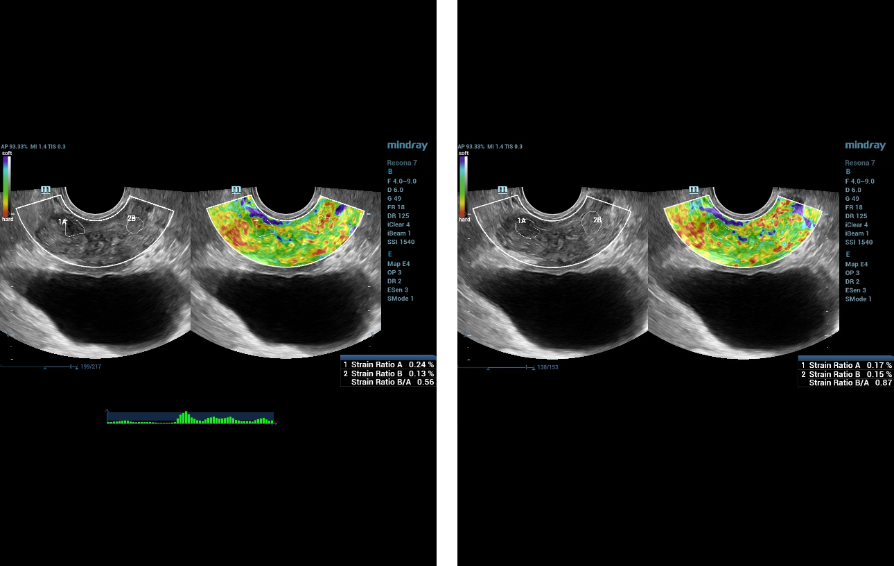

Strain Elastography Findings

Using Natural Touch Elastography on the Resona 7 the stiffness of the prostate gland was assessed. The hypoechoic lesion within the peripheral zone did not show as significantly stiffer than the surrounding tissue with a Strain Ratio measuring between 0.56-0.87.